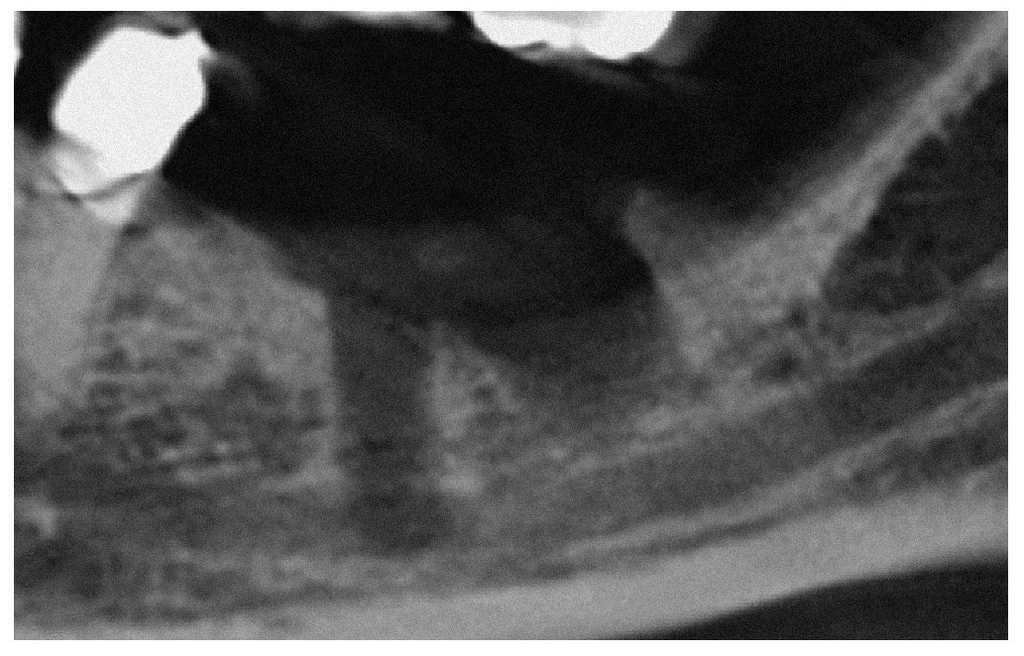

La radiografía panorámica muestra la situación después de la inserción del primer implante, que se proyecta nítidamente sobre el conducto dentario inferior (fig. 1). Después de retirar el implante, se realizó una tomografía volumétrica digital dental. En ésta se observa una perforación cuya parte superior se sitúa en lingual del conducto dentario inferior y, la inferior, penetra en el conducto dentario inferior desde lingual (figs. 2 a 4). Más de 1 año después de la inserción del implante sigue persistiendo la sensación de entumecimiento completo.

Figura 4. Tomografía volumétrica digital dental - plano transversal.